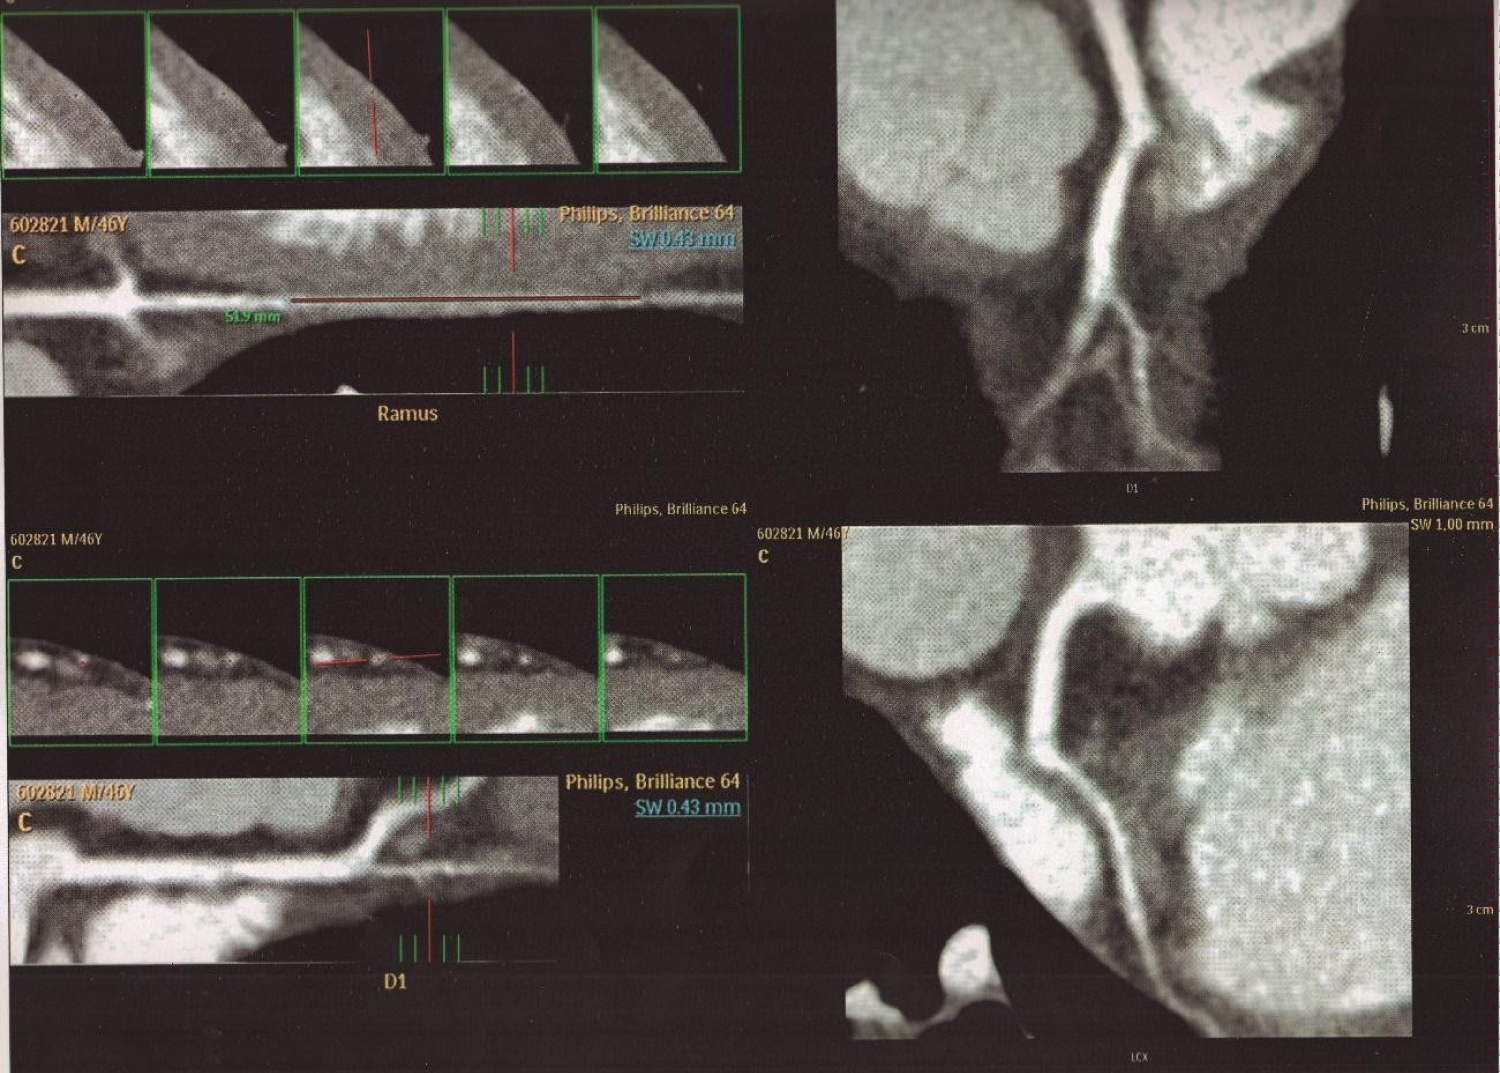

Figure 4: Cardiac multislice angiotomography. Coronary artery calcium score was 0. Left anterior descending artery without atherosclerotic lesions. (A) Showed in Ramus intermedius artery of moderate size with a deep intramyocardial course (MB); (B) The first diagonal artery without atherosclerotic lesions with intramyocardial course in distal third (MB). Circumflex artery, without lesions Right coronary artery dominant without lesions.

MB: Myocardial Bridge.

Figure 5: Additional analysis of the myocardial bridge in the ramus intermedius artery and first diagonal artery showed in Figure 4 with CTTA. Cross-sectional view in an extended intramyocardial course (MB) in RI artery (51.9 mm); and in the first diagonal artery.

CCTA: Cardiac Computed Tomography Angiography; MB: Myocardial Bridge; RI: Ramus Intermedius